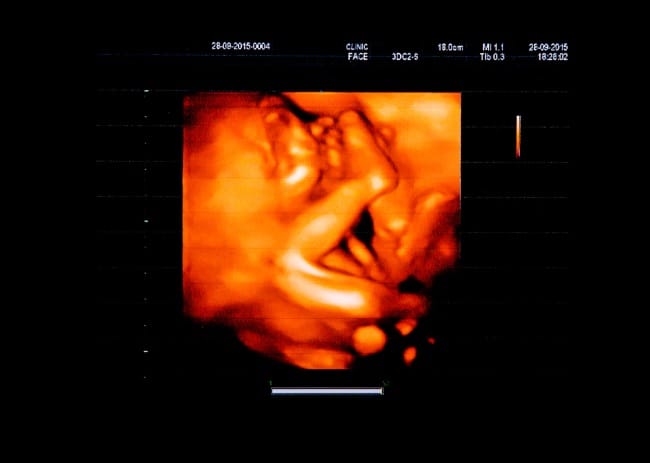

Pada usia kehamilan 5 bulan atau sekitar 20 minggu, berat janin yang dianggap normal umumnya berkisar antara 260–320 gram, serta panjang tubuhnya sekitar 16-19 cm dari kepala sampai tumit. Umumnya, berat dan pertumbuhan lain pada janin terlihat melalui pemeriksaan USG. Makanya, pemeriksaan ini penting untuk dilakukan secara rutin.

Selain untuk memantau berat badan janin, pemeriksaan USG secara rutin juga dilakukan untuk mendeteksi lebih awal jika terjadi gangguan pada pertumbuhan janin, misalnya intrauterine growth restriction (IUGR) atau makrosomia. Apabila ternyata ada, dokter akan mencari tahu penyebabnya, misalnya karena asupan nutrisi ibu yang kurang, sehingga penanganan bisa segera dilakukan.